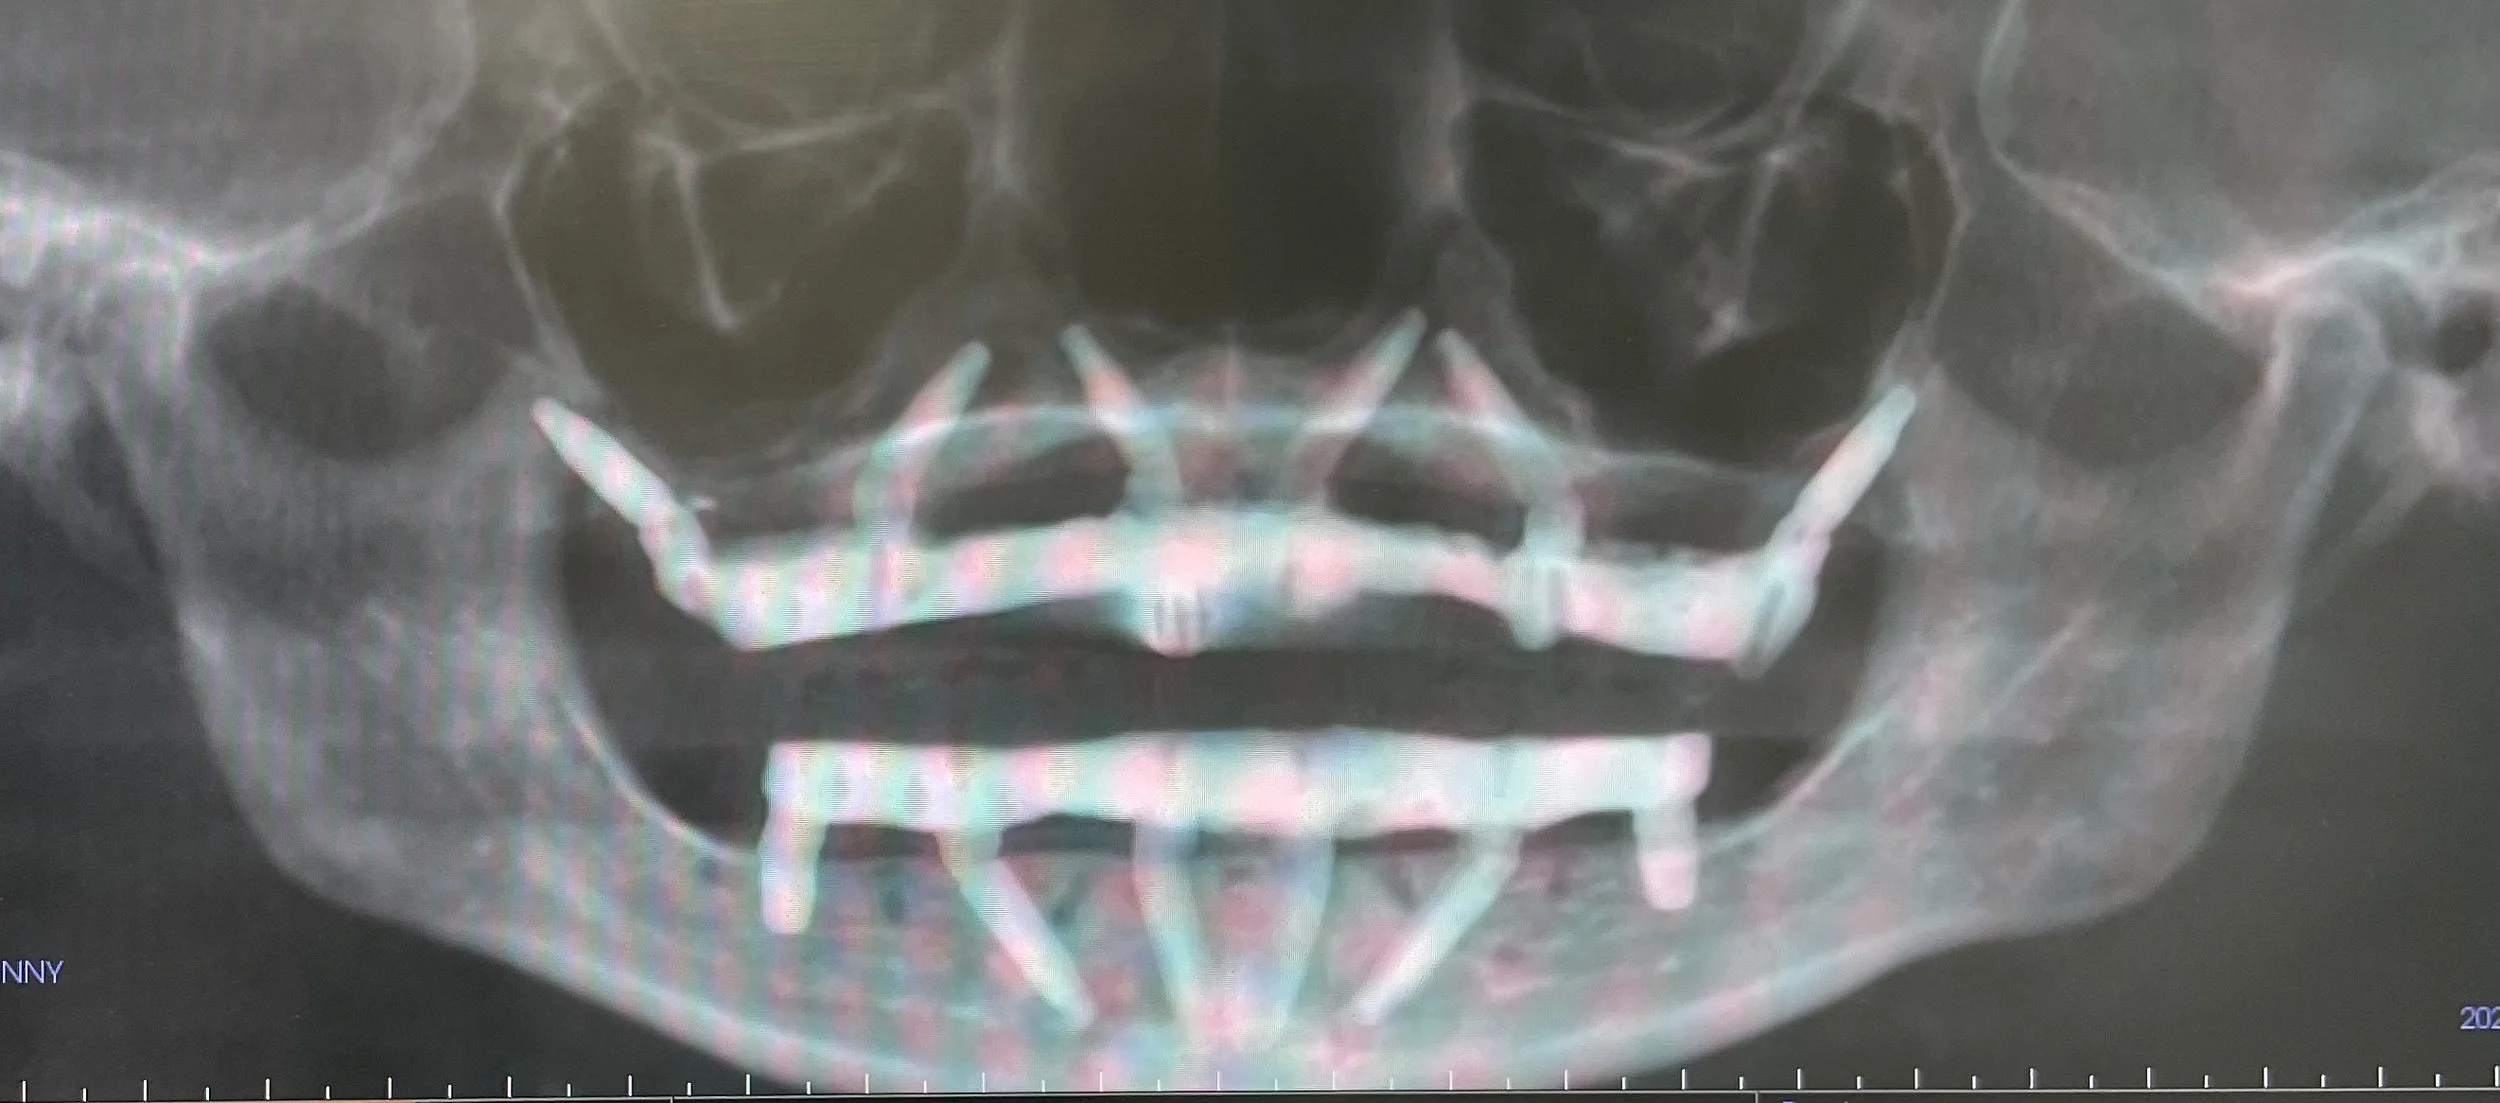

Dr. Damons Cases